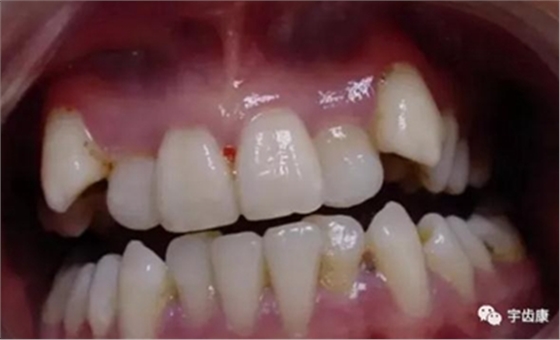

牙體解剖知識

牙體各個面的解剖厚度